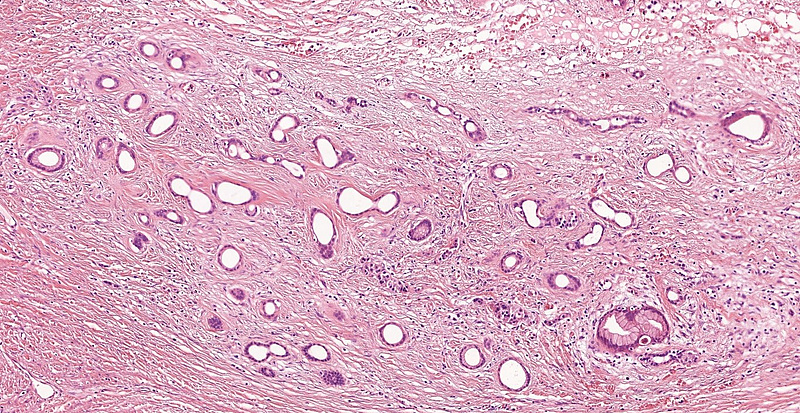

The operation specimen showed a well-circumscribed, multilocular, cystic lesion measuring 35 mm in largest dimension. Microscopic examination showed intraductal / intracystic papillary proliferations. The cells were reminiscent of gastric foveolar epithelium with apical mucin cap and mild atypia. Focal oncocytic change was also visible. Ovarian-like stroma was not detected. Intestinal or pancreatobiliary differentiation as well as invasive components were not identified (Panels A-C).

Immunohistochemistry demonstrated diffuse positivity for MUC5AC (Panel D). MUC6 was focally positive within the oncocytic component of the tumour (Panel E). Of note, intra- and interlobular fibrosis with remarkable atrophy of the acini was detected in the non-neoplastic area of the pancreas, mimicking well-differentiated (tubular) invasive carcinoma (Panel F). Endocrine cells were comparatively spared and the lobocentric architecture was preserved.